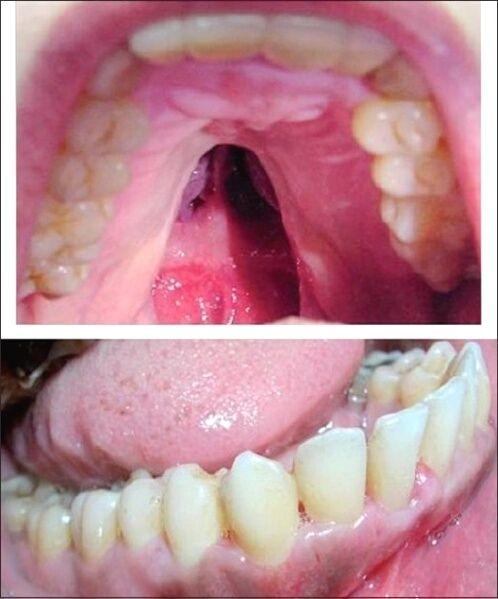

软腭裂是什么症状

腭裂分度与分型图片